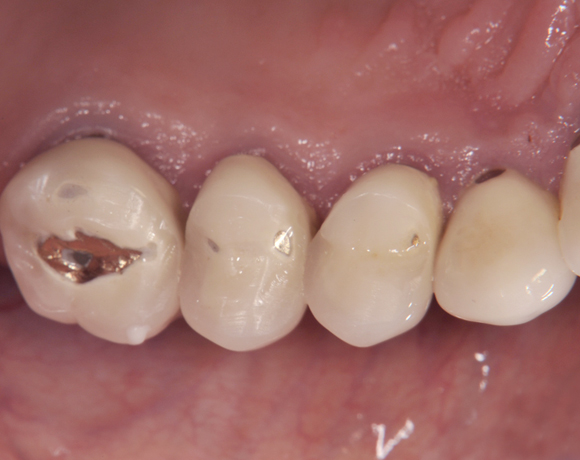

Der vorliegende Patientenfall zeigt eine komplette Neuversorgung der vorhandenen Metallkeramikkronen mit vollkeramischen Restaurationen. Zusätzlich wurde im Oberkiefer die Zahnreihe mit zwei Implantaten, für die fehlenden Molaren, ergänzt. Da keine ausreichende Knochenhöhe vorhanden war wurde ein interner Sinuslift geplant.